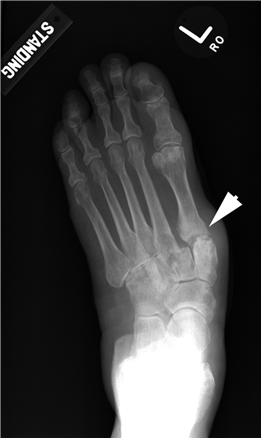

Weight-bearing anteroposterior (AP), lateral, and sesamoid axial radiographs are mandatory. On the AP view, the surgeon measures the Hallux Valgus Angle (HVA, normal < 15°), the Intermetatarsal Angle (IMA, normal < 9°), and the Distal Metatarsal Articular Angle (DMAA). The lateral view is scrutinized for Meary's angle (talo-first metatarsal angle) to identify midfoot collapse, as well as the presence of dorsal osteophytes indicative of hallux rigidus. The sesamoid axial view is critical for assessing the degree of sesamoid subluxation and the integrity of the crista.

When conservative measures fail, the choice of procedure is dictated by the severity of the deformity, the presence of degenerative joint disease, and the stability of the first TMT joint. Distal osteotomies (e.g., Chevron) are generally reserved for mild to moderate deformities with an intermetatarsal angle (IMA) less than 13 degrees. Diaphyseal osteotomies (e.g., Scarf) offer greater translational correction for moderate to severe deformities. Proximal procedures, such as the Lapidus arthrodesis, are indicated for severe deformities (IMA > 15 degrees), clinical hypermobility of the first TMT joint, or recurrent hallux valgus. For hallux rigidus, joint-sparing procedures like cheilectomy are indicated for early-stage disease, while first MTP arthrodesis remains the gold standard for end-stage arthritis.